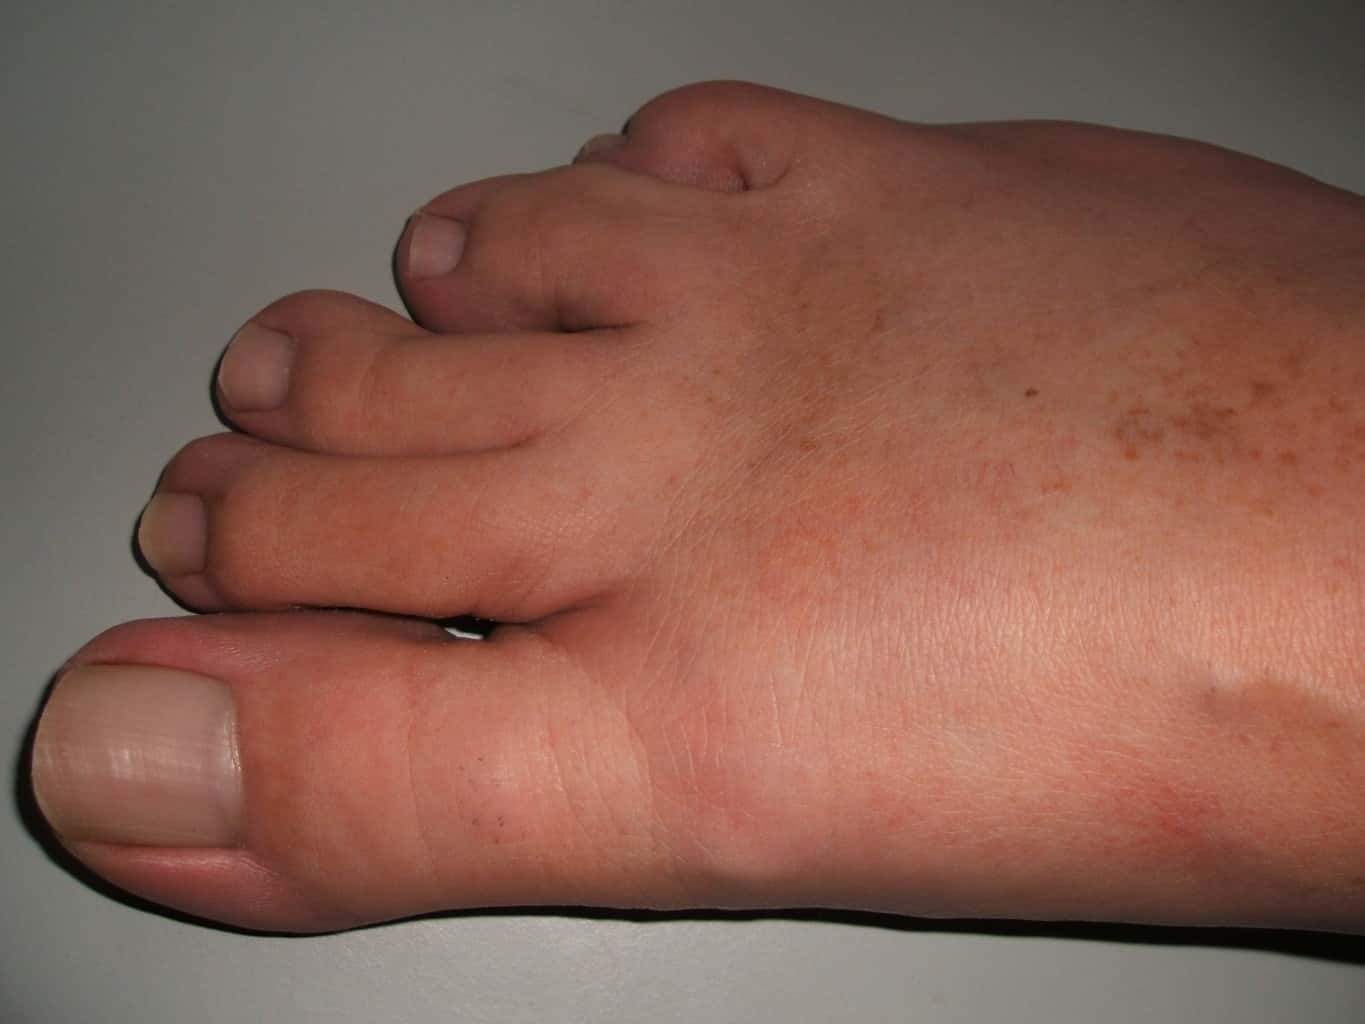

#39 I'm Fine

Kinda opposite to what everyone is saying, but I once saw a guy with a foot that looked like death (probably untreated diabetic). He only went to the ER because his sons dragged him. He literally had his foot inside a plastic bag because of the smell. He insisted he was fine and to be let go. The amount of horribly sick patients that think they're "just fine" is too high!